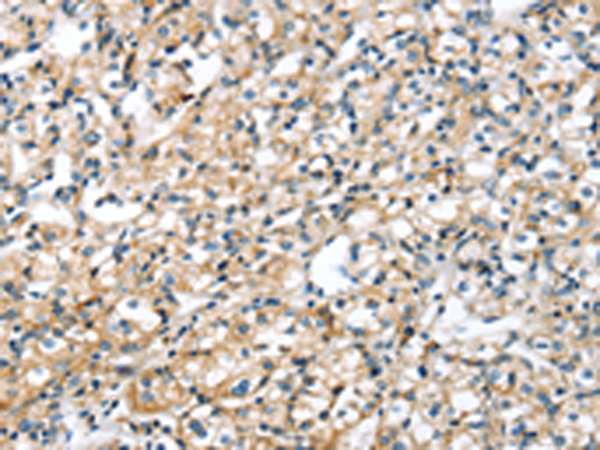

分类: 科研抗体货号: P00153别名: ANG2; AGPT2应用: WB,IHC反应种属: Human, Mouse, Rat